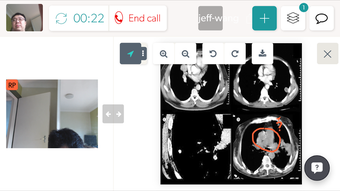

COVIU - это бесплатное приложение для Android, которое предоставляет платформу для видео-сотрудничества. Это приложение предлагает простой и интуитивно понятный интерфейс, который позволяет всем делиться и аннотировать файлы, доски или свой экран. Это отличный инструмент для членов команды, партнеров и клиентов.

Еще одна отличительная особенность COVIU - это возможность приглашать людей присоединиться к вашему звонку, просто поделившись вашим URL-адресом Coviu. Это упрощает подключение к другим и совместную работу над проектами. В целом, COVIU - это фантастическое приложение для всех, кто ищет надежный и безопасный инструмент для видео-сотрудничества.